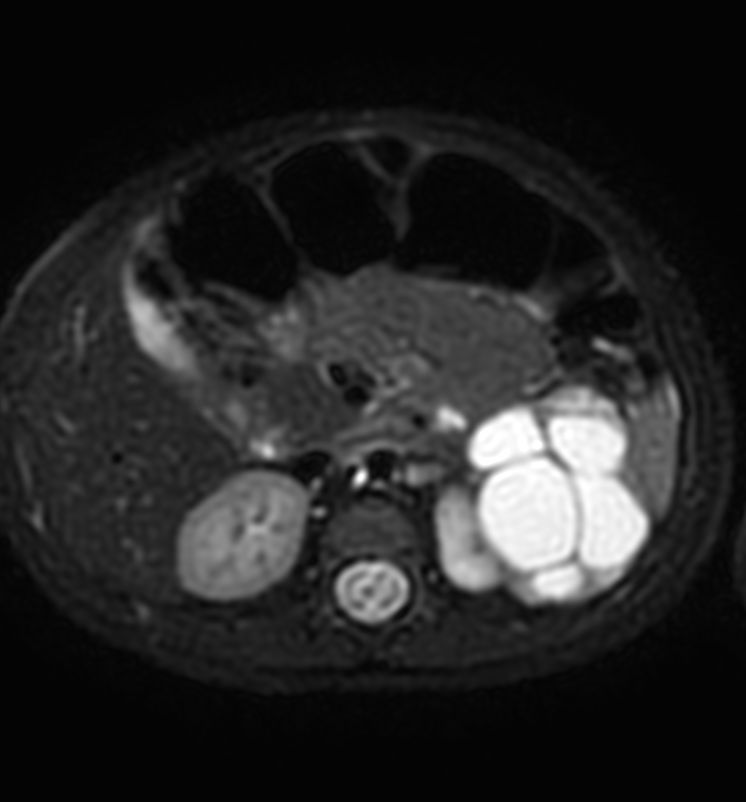

3D VIEW T2w SPIR - Axial reformat